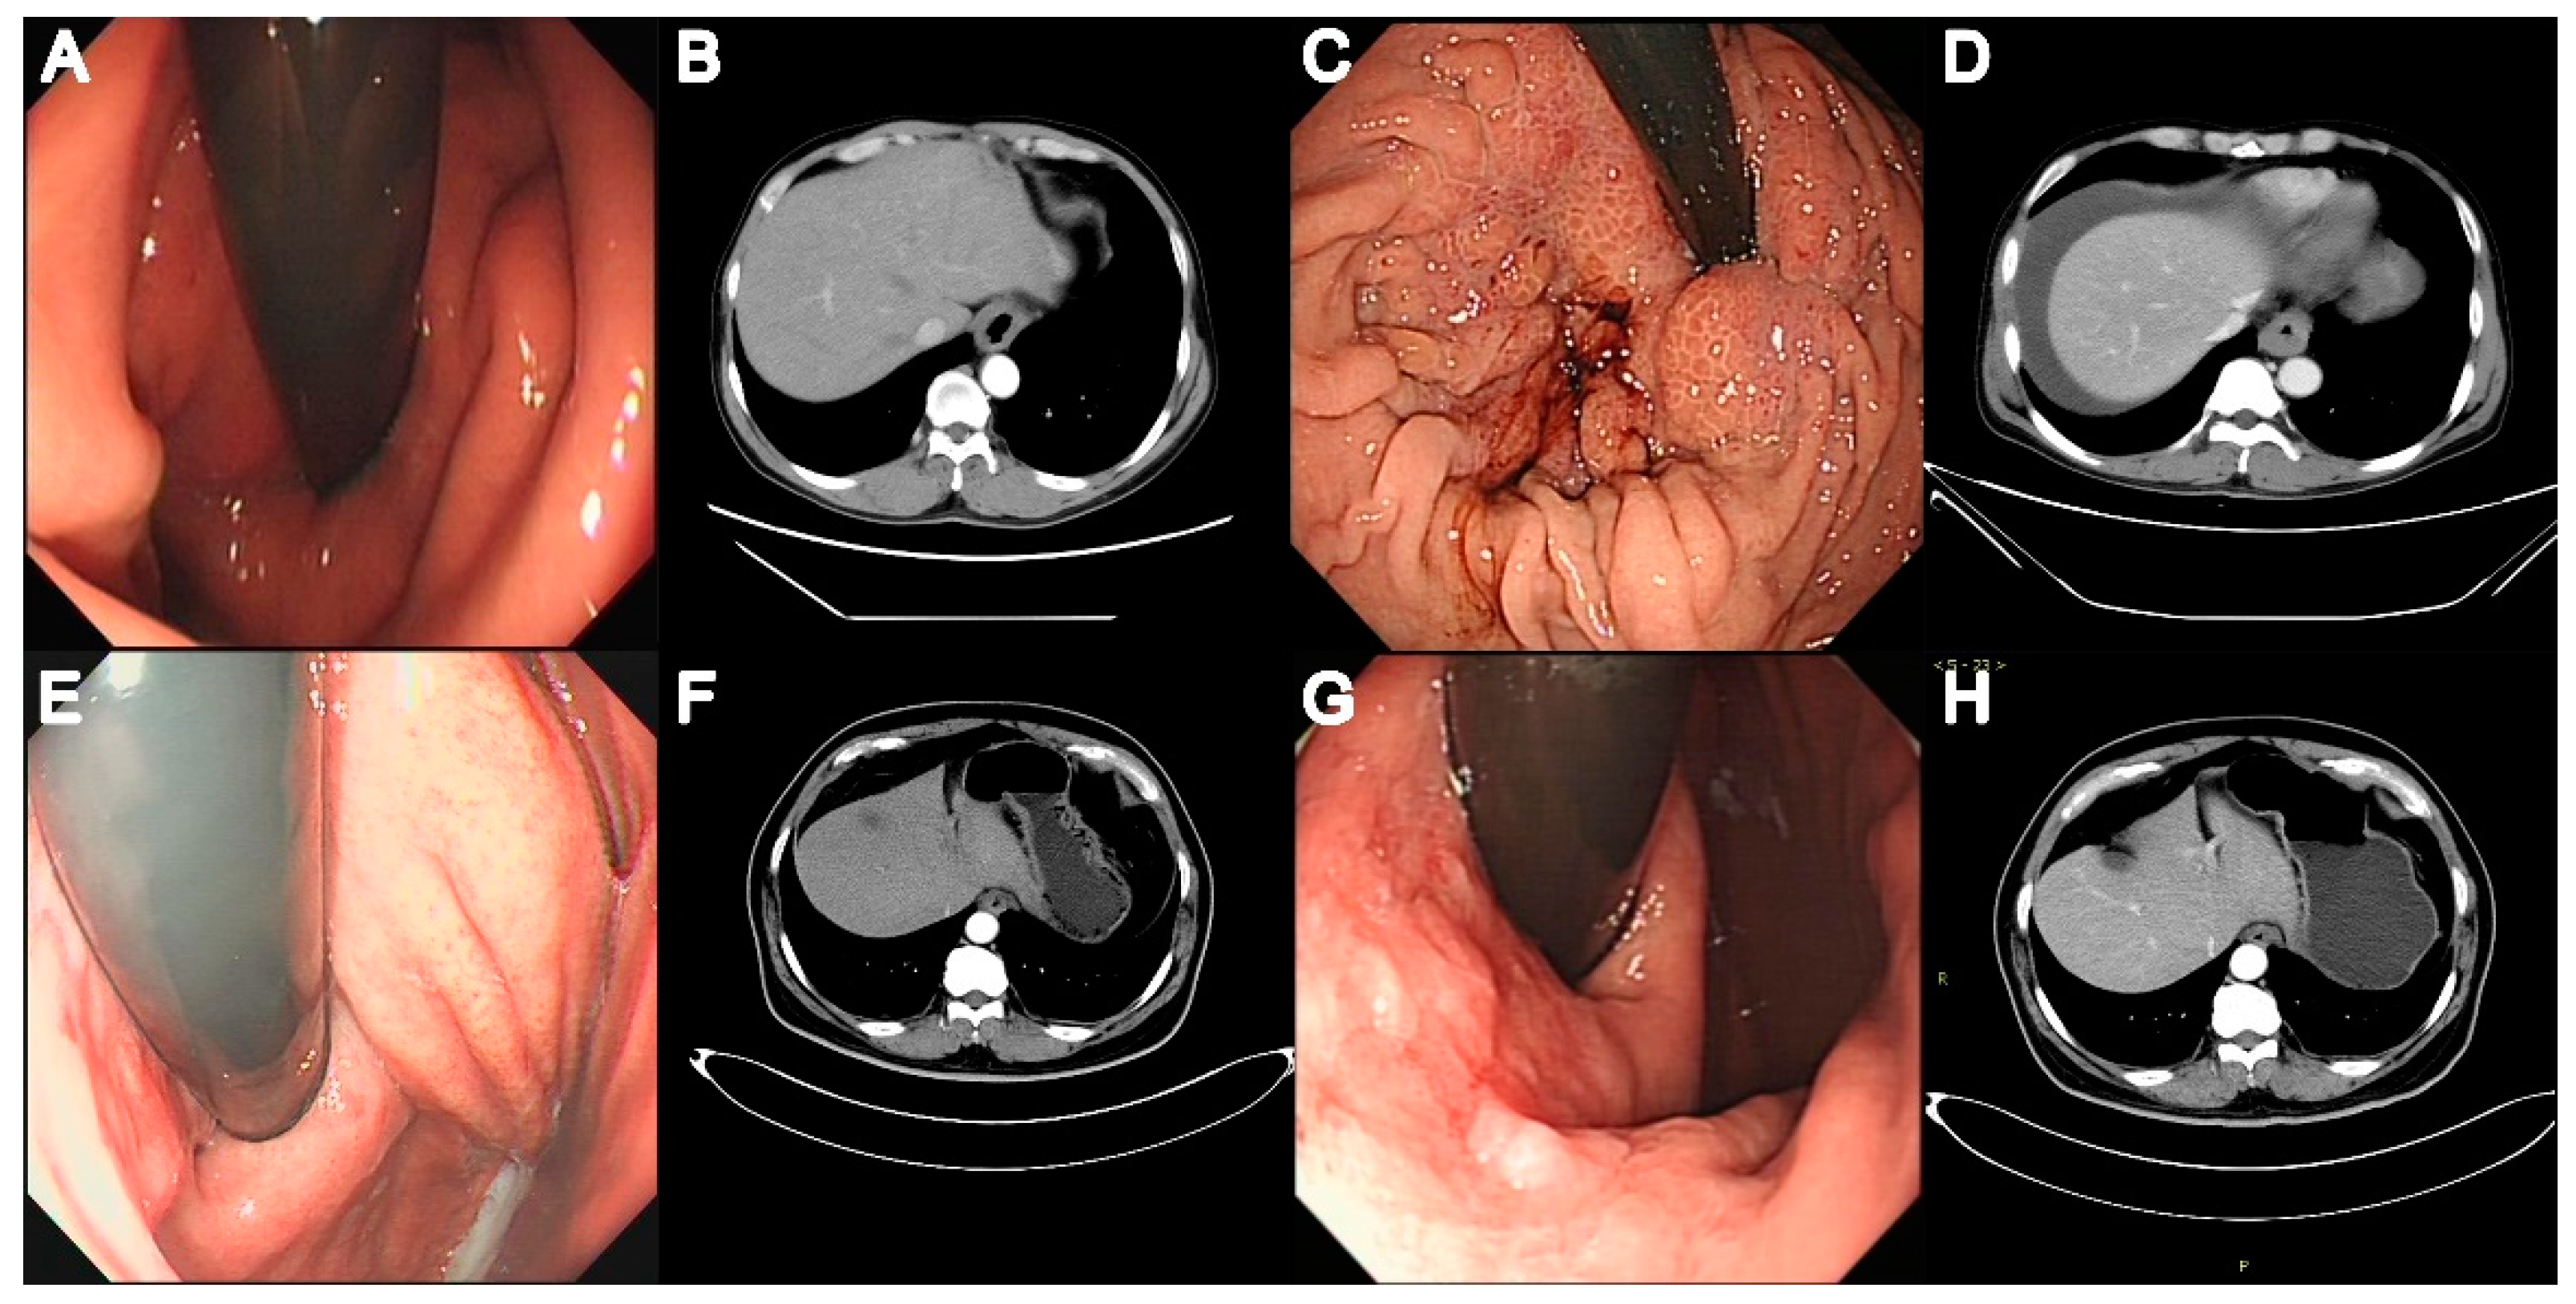

A total of 149 patients (79 with AC, 70 with EGJOO) were included in this study. Figure 1 shows the patient selection process. The median follow-up was for 28 (22–36) months. Of the 79 patients with AC, 5 (6.33%) had AC type 1, and 74 (93.67%) had AC type 2. Table 1 lists the conditions concomitantly present in patients with EGJOO and AC. Concomitant AEG and autoimmune diseases were significantly more common in EGJOO (p = 0.021 and p = 0.026). The concomitant autoimmune diseases in EGJOO included rheumatoid arthritis (three patients), Sjogren syndrome (two patients), and dermatomyositis (two patients). One patient with AC had concomitant hypothyroidism. A family history of cancer of the esophagus, EGJ, or stomach was significantly more common in patients with EGJOO (p = 0.002). Of note, 5/70 (7.14%) patients with EGJOO were diagnosed with AEG during follow-up. Figure 2 shows the endoscopic and CT images of the two patients with EGJOO and subsequent AEG.

Figure 2.

Endoscopic and computed tomography (CT) scan images of two patients with EGJOO and subsequent adenocarcinoma of the esophagogastric junction (AEG). Patient 1 was diagnosed with cardia inflammation using endoscopy (A) and pathology. Thickened cardiac wall and slight stricture of the esophagus are seen on CT (B) performed at the initial visit. Six months later, AEG (T3N0M1) was diagnosed. Endoscopy shows coarse, hyperemic, and easily bleeding cardia mucosa (C). CT shows an obviously thickened cardiac wall (D). In Patient 2, endoscopy performed at the initial visit (E) shows cardia mucosa hyperemia; CT (F) shows a slightly thickened cardiac wall. Endoscopy (G) performed one-and-a-half years later shows high-grade localized intraepithelial neoplasia in the gastric mucosa; this was confirmed on pathology. CT shows thickened and enhanced cardiac wall (H).